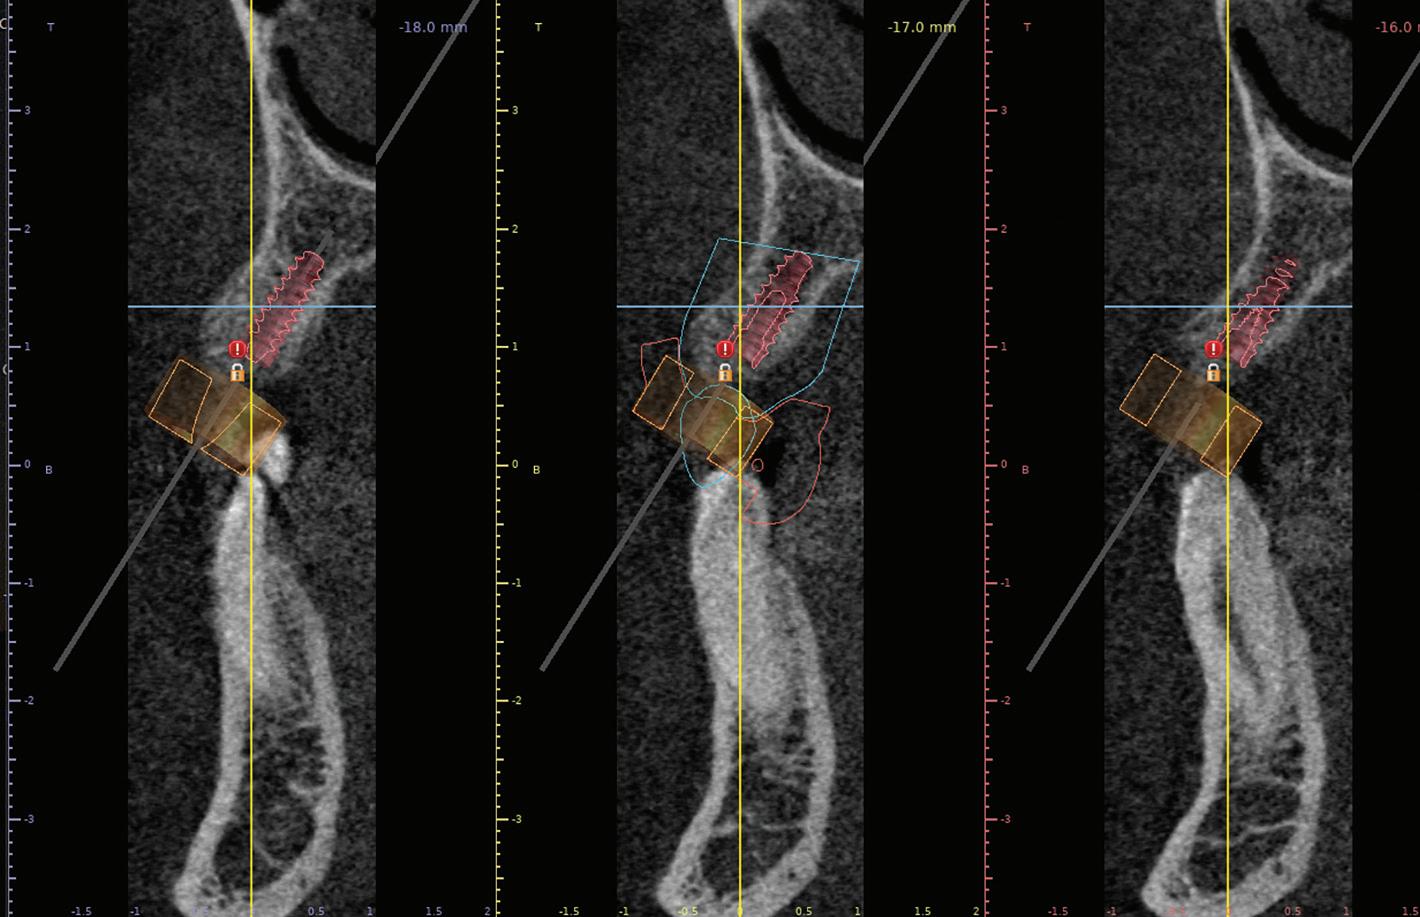

After tooth extraction and socket preservation, patients heal for at least 3 to 4 months. Once the healing process is complete, among the most important procedures for implant planning are cone beam computed tomographic (CBCT) and intraoral scans. The CBCT scan is a 3-dimensional (3D) radiograph that shows the patient’s bone in ways that cannot be seen on 2-dimensional images such as periapical, bitewing, or panoramic radiographs. The use of CBCT scans for implant cases is becoming common because of the important information provided, including bone height, bone width, and the location of arteries, veins, nerves, and other important anatomical features.2

In addition, CBCT images can be used to assess bone density. Bone density ranges from D1 to D4.3 The density is measured in a ratio of cortical-to-cancellous bone. Cortical bone, which makes

up the outer portion of the bone, is dense and has low vascularity. Cancellous bone, which makes up the inner portion of the bone, is not dense and has higher vascularity. D1 bone consists of a high percentage of highly dense cortical bone and minimal to no cancellous bone. D4 bone has a high percentage of low-density cancellous bone and little to no cortical bone. In bone that is more cortical and more dense, the clinician will generally make a larger osteotomy to reduce the stress put on the dense bone. In bone that is less dense and more trabecular, the clinician can make a more undersized osteotomy to ensure good primary stability of the implant. Depending on the type and density of bone found on the preoperative CBCT, the clinician can modify the implant placement technique to adjust for the findings. In my experience, the density of grafted sites is usually classified as D2, but this can vary depending on the type of graft used (Fig 1 and 2).

contacts, the restoration can be easily seated. When the long axis of the implant is not aligned with the proximal contacts of the adjacent teeth, it may not be possible to use a screw-retained restoration. In select cases, a cement-retained restoration may be necessary. Figure 3 shows implant planning performed using the CBCT images and intraoral scans. The proposed implant is placed in a biologically sound position, and the blue outline of the digital wax-up tooth can be seen. This angled positioning in the esthetic zone would have resulted in an access hole in the facial surface, which is unesthetic. This means that this case will need a cement-retained crown. Using the information from the CBCT and intraoral scans, we know this from the beginning of the case so the restorative portion of the case can be planned accordingly. If the position of the implant had been adjusted enough to place a screw-retained restoration, the result would have been a notable apical perforation, and several millimeters of the implant apex would be outside the bony housing. This would significantly complicate the case and require at least 1 additional grafting surgery, and grafting outside the bony housing is unpredictable. After taking all factors into consideration, it was decided to plan to restore with a cement-retained crown instead of undergoing further surgical procedures.

Fig 1. CBCT images confirm healing of the extraction site after grafting. Fig 2. An occlusal CBCT view reveals the density of the healed graft.

Fig 3. CBCT images of the proposed implant at the site. The digital wax-up can be seen outlined in blue. Placing the implant in a biologically sound position yields a restoration with facial screw access, making a screw-retained restoration an unesthetic option.